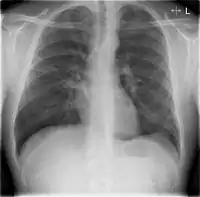

Chest X-rays and X-ray computed tomography (CT) can reveal areas of opacity (seen as white), indicating consolidation.[13] CAP does not always appear on x-rays, sometimes because the disease is in its initial stages or involves a part of the lung not clearly visible on x-ray. In some cases, chest CT can reveal pneumonia not seen on x-rays. However, congestive heart failure or other types of lung damage can mimic CAP on x-ray.[15]

Chest X-rays of a CAP patient before (left) and after treatment

CAP is treated with an antibiotic that kills the infecting microorganism; treatment also aims at managing complications. If the causative microorganism is unidentified, which is often the case, the laboratory identifies the most effective antibiotic; this may take several days.

Ceftriaxone and azithromycin are often used to treat community acquired pneumonia, which usually present with a few days of cough, fever, and shortness of breath. Chest x-ray typically reveals a lobar infiltrate (rather than diffuse).[19]